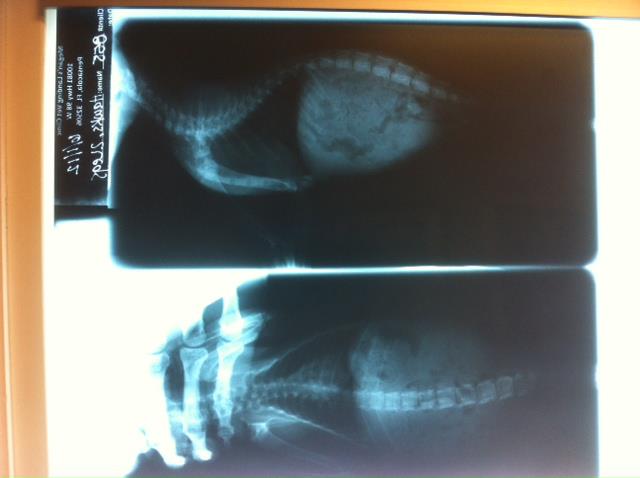

The exam showed that Anakin is approximately 6 to 8 weeks old and actually in excellent health. Two x-rays show he was born with no pelvis or back legs. They allowed him walk around the room for a minute to observe and study how he moves. He positions his front legs at an angle towards the middle of his body and balances his back end in the air with the use of his tail touching the ground if he needs it. It is a method that seems to work very well for him. Thankfully, the x-ray also showed that his organs were not malformed. The feline leukemia test came back negative so Carrie got him vaccinated, de-wormed and some flea med’s and took him to his new home.